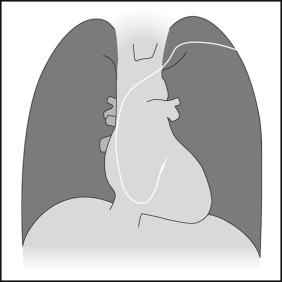

Endocardial Pacer Leads

The position and integrity of endocardial pacer leads should be verified, especially when pacemaker dysfunction is clinically suspected ( Graphics 23-1 to 23-4 ; Figs. 23-1 to 23-15 ).The most common cause of pacemaker dysfunction that is apparent on the chest radiography is distal lead displacement/misplacement.

With a right atrial lead , the tip should be in the right atrial appendage.

With a right ventricular lead , the tip should lie anteriorly at the apex of the heart.